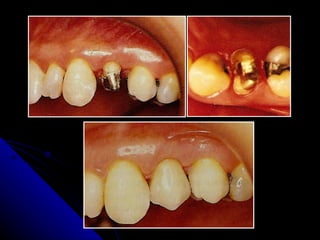

LIMITE CERVICAL DAS RESTAURAÇÕES PROTÉTICAS Limite cervical das restaurações protéticas relaciona com: Fatores estéticos:  afim de esconder a linha de junção.  Fatores mecanicos  :1   - aumento de retenção de dentes curtos ou parcialmente destruídos  2- presença de cárie,  3 - erosões,  4- fraturas,  5- sensibilidade dentinária .

LIMITE CERVICAL DASRESTAURAÇÕES PROTÉTICAS Limite cervical das restaurações protéticas relaciona com: Fatores estéticos: afim de esconder a linha de junção. Fatores mecanicos :1 - aumento de retenção de dentes curtos ou parcialmente destruídos 2- presença de cárie, 3 - erosões, 4- fraturas, 5- sensibilidade dentinária .

Preparos sub-gengivais:   -Existem  maiores riscos de  distorções no ajuste da restauração. -Torna-se  difícil  obter uma linha de terminação definida e polida. - Dificuldade na adaptação da prótese provisória .  - A moldagem vai necessitar  de manobras específicas de afastamento gengival